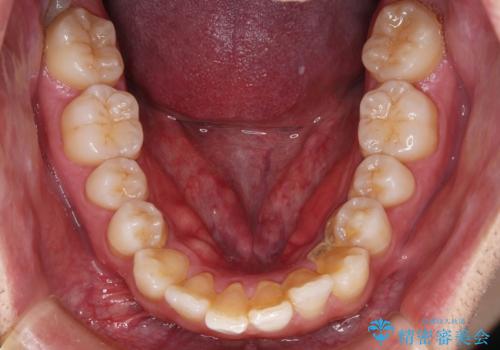

- 上の歯が出ているのが気になるのを主訴にご来院されました。人前で話すお仕事をされており目立たないマウスピース治療を希望されていました。

IPR(歯と歯の間を削る処置)と歯列拡大をすることで前歯を少し下げ、がたつきを改善していく治療計画を立てました。

上の前歯が出ているという主訴が綺麗に改善されました。

その他の部位のがたつき、奥歯の噛み合わせも以前と比べると良くなっています。